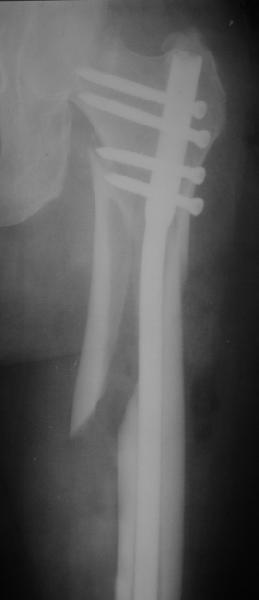

Это было года 2,5 назад, мы тогда еще уточняли возможности шинирования с угловой стабильностью гвоздем с поперечным расположением винтов при переломах проксимального отдела бедра. Пациенту не пришлось приобретать намного более дорогой рекон или проксимальный гвоздь. В приложении еще несколько примеров применения того гвоздя при высоких переломах бедра, в том числе с более латеральной точкой входа. Гвоздь изгибаем для этого.